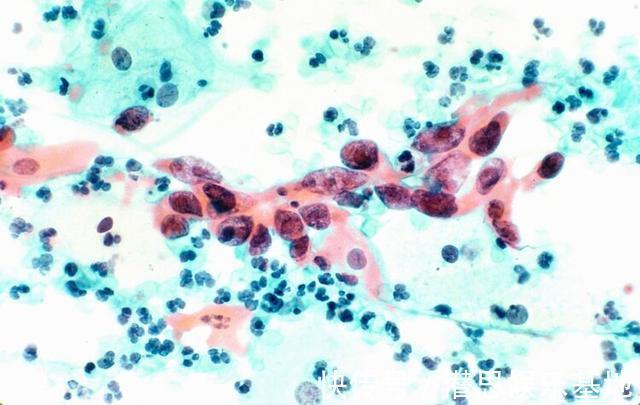

文章插图